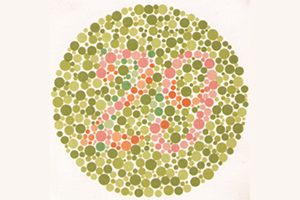

Wie werden Farbsinnstörungen festgestellt?

Um Farbsehstörungen zu diagnostizieren, kann eine orientierende Überprüfung des Farbsinns mit bestimmten Farbtafeln (Ishihara-Tafeln) durchgeführt werden. Die Zahlen werden vom Betroffenen teilweise nicht oder falsch erkannt. Die Feststellung, welche der dargebotenen Zahlenproben nicht richtig gelesen werden, lässt auf die Art der vorliegenden Farbsehstörung schließen. Am so genannten Anomaloskop können außerdem spektrale Lichter gemischt und verglichen werden. Der Farbsehgestörte schaut durch ein Rohr auf eine zweigeteilte Prüfscheibe, deren untere Hälfte er mit einer Mischung von Rot und Grün so einstellen muss, dass sie der oberen gelben Hälfte entspricht. Je nach Farbsehstörung wird er zu viel von einer Farbe zugeben und ein für ihn vergleichbares Gelb erzeugen. Seine Farbsehstörung kann somit objektiviert werden.

Analyse von Farbsinnstörungen